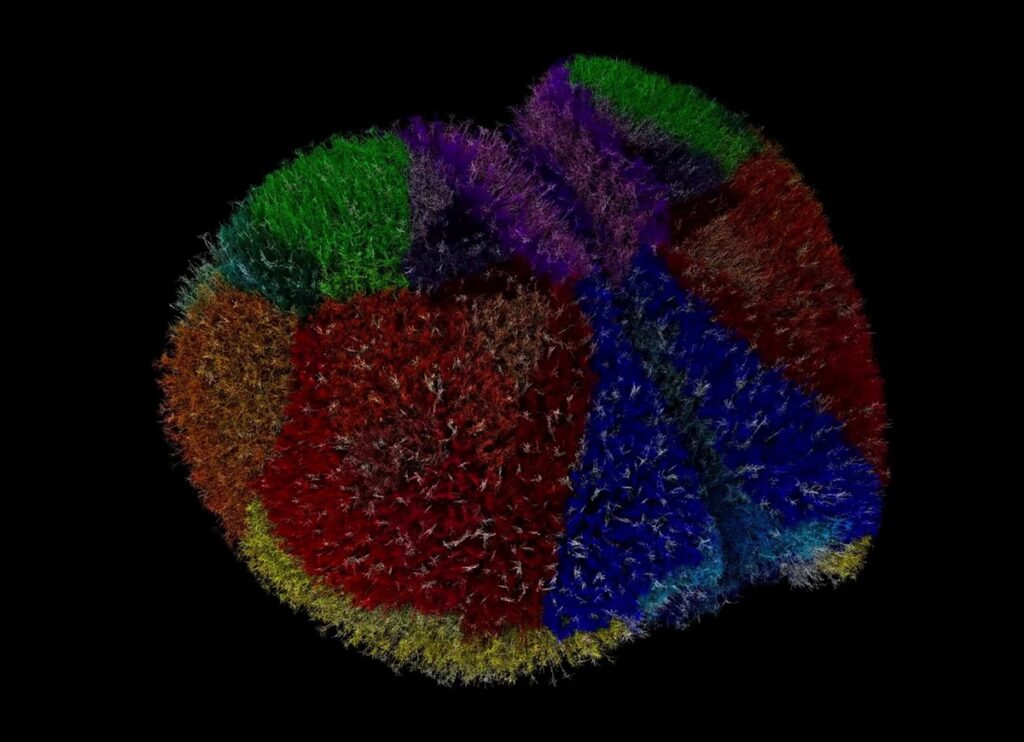

Вчені створили одну з найповніших і найбільш біологічно достовірних симуляцій мозку тварини, а саме миші, використовуючи один з найшвидших суперкомп’ютерів у світі. Ця цифрова реконструкція кори мозку миші дозволяє моделювати нейродегенеративні захворювання, епілепсію та інші стани у віртуальному середовищі. У симуляції відтворено майже 10 мільйонів нейронів, 26 мільярдів синапсів та 86 взаємопов’язаних ділянок мозку з високою точністю. Проєкт був реалізований за допомогою суперкомп’ютера Fugaku, який здатний виконувати квадрильйони операцій за секунду. Ця симуляція дозволяє вченим вивчати природу неврологічних розладів та механізми роботи мозку. Високодеталізована модель мозку миші допомагає розуміти процеси, які відбуваються в мозку, і дозволяє проводити дослідження без експериментів на живих тваринах. Цей технічний прорив підтверджує, що масштабні й точні моделі мозку стають доступними, відкриваючи шлях для майбутніх досліджень і розвитку повної моделі мозку людини.